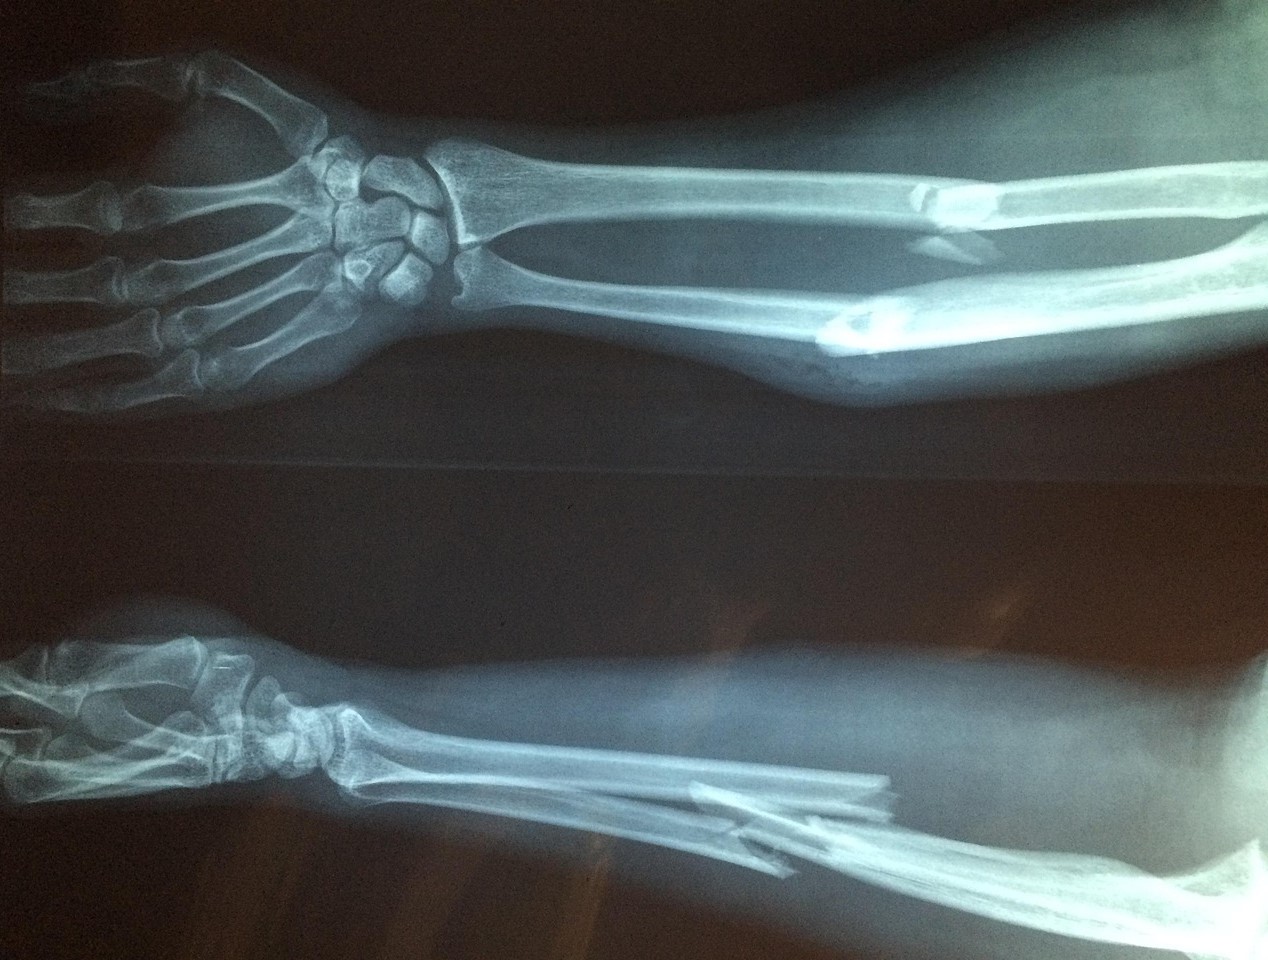

October 20 is World Osteoporosis Day. Osteoporosis is vastly underdiagnosed and remains untreated in millions of people worldwide. Every year, about 190,000 older Australians are admitted to hospitals or community services for an osteoporotic fracture, costing the taxpayer several billion annually. Osteoporosis is a silent disease, as most don’t know they have it till they have a fracture after a minor fall or bump. Most of these fractures could have been prevented with early intervention and good medical management. Shockingly, however, an older person who has suffered an osteoporotic fracture has an 80-90% chance of NOT being investigated and/or treated for the disease causing these fractures. As a result, these people will sustain more fractures, pain and disability. 20-30% of people die within 12 months of suffering a hip fracture.

Every year, about 190,000 older Australians are admitted to hospitals or community services for an osteoporotic fracture, costing the taxpayer several billions annually. Osteoporosis is a silent disease as most don’t know they have it till they have a fracture after a minor fall or bump. Most of these fractures could have been prevented with early intervention and good medical management. Shockingly, however, an older person who has suffered an osteoporotic fracture has a 80-90% chance of NOT being investigated and/or treated for the disease causing these fractures. As a result, these people will sustain more fractures, pain and disability. 20-30% of people die within 12 months of suffering a hip fracture.